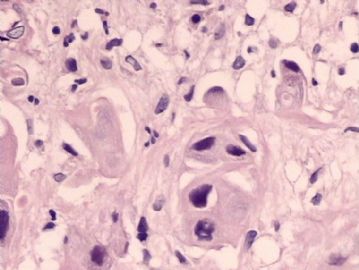

腺鳞癌?

姓    名: ××× 性别:   年龄:  39岁

标本名称:  宫颈活检

简要病史:  同房出血3次,tct HSIL

考虑:原位腺癌,小灶性区域有鳞状上皮向间质内浸润,考虑有鳞状细胞癌结构。

• 腺鳞癌?图4

图4